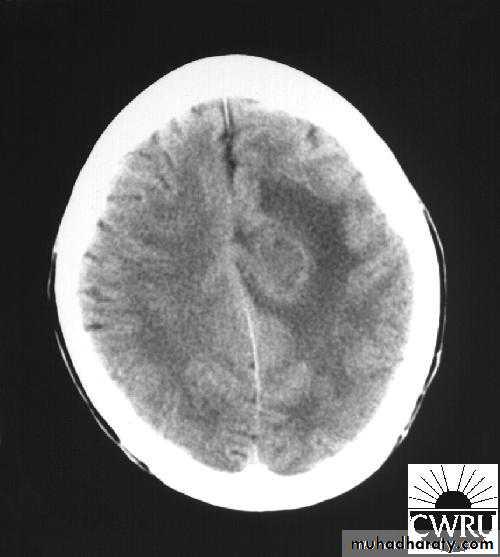

Brain Abscess

• B. Radiological Investigations:

• CT or MRI is the investigation of choice.

• CT Brain is performed with and without contrast.

• MRI is done with gadolinium enhancement.

• They will show a single (or multiple) space occupying lesion that is well delineated with an enhancing wall, with variable surrounding oedema.

Brain Abscess CT without contrast

Brain Abscess CT with contrast